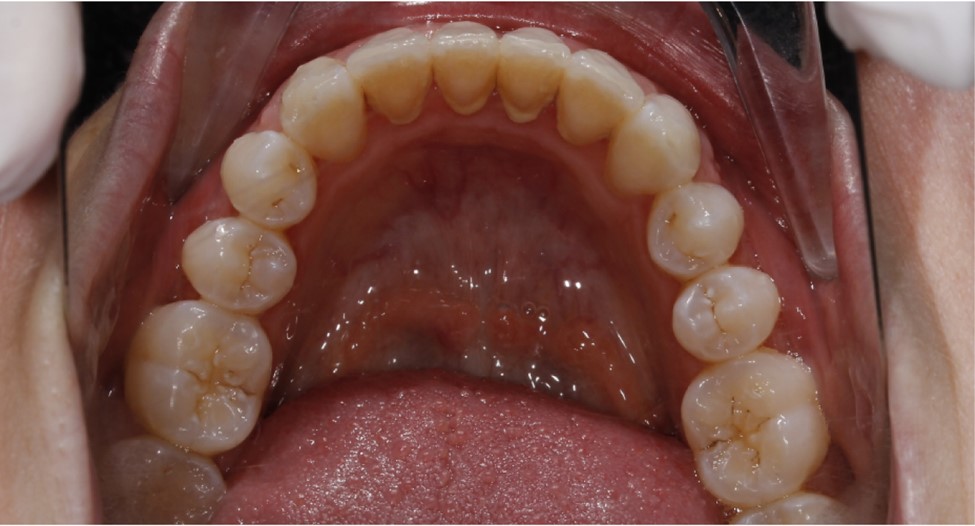

چگونه متوجه می شوید که دندان های شما جابجا شده اند؟

فراتر از نشانه های واضح کج شدن دندان هایتان، شواهدی مبنی بر جابجایی دندان هایتان پس از ارتودنسی می توانند شامل موارد زیر باشند:

• تنگ بودن یا نامناسب بودن نگهدارنده. متخصص ارتودنسی شما نگهدارنده را به صورت سفارشی برای شما می سازد تا کاملاً با دندان های مرتب شما مطابقت داشته باشد. بنابراین، اگر نگهدارنده شما سفت به نظر می رسد یا دیگر مناسب نیست، این نشانه قطعی جابجایی دندان های شما است. متأسفانه، این معمولاً به دلیل استفاده ناکافی از نگهدارنده شما است.

• فاصله بین دندان ها. این یک نشانه شایع و قابل تشخیص است که دندان های شما در حال جابجایی هستند. فاصله ها همچنین ممکن است نشانه ای از مشکلات پریودنتال (لثه) در حال پیشرفت باشند.